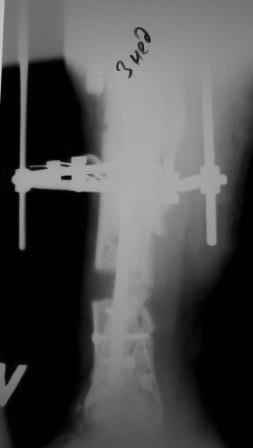

3) Третьим этапом наложили модуль на промежуточный фрагмент.(рис 3) И начали его транспорт на стержне в проксимальном направлении. (рис 3 а)

Надеемся что «вырастет» регенерат в дистальном отделе, а в проксимальном отделе фрагмент «упрется» и прирастет.